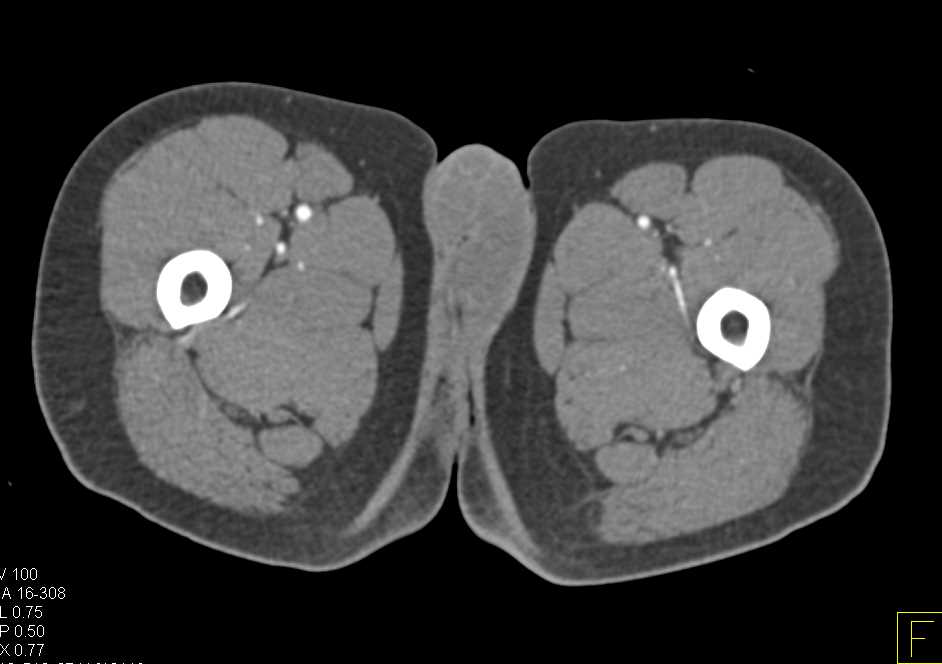

May-Thurner Syndrome (MTS) with Stents in Place